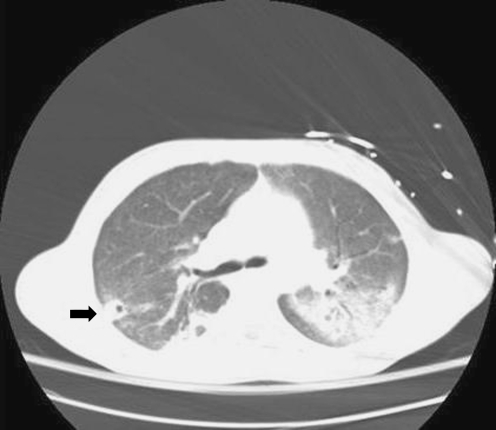

On hospital day 2, the patient underwent operative irrigation and debridement, with evacuation of a large amount of purulent material followed by serial culture, incisement, and drainage of affected soft tissues, with limited resection of necrotic bone. Tissue and blood cultures were positive for Fusobacterium necrophorum, an anaerobic gram-negative bacillus. Despite repeated operative irrigation and debridement of the left hip, the patient remained persistently febrile. This occasioned duplex ultrasoundography of the neck and carotids vessels, which failed to reveal evidence of thrombus formation. However, repeat left lower extremity CT demonstrated local thrombus progression necessitating thrombectomy. As thrombus was extracted from segments involving the deep popliteal fossa and distal common iliac vein, concern for central embolization arose again. A repeat chest CT demonstrated small areas of cavitation throughout the dependent infiltrates, suggesting that the infiltrates were at least partially due to septic emboli (Fig. 6). Eventually, the patient recovered after prolonged antibiotics and multiple debridement procedures with the involved limb salvaged intact.

Fig. 6.

CT scan of the chest with contrast demonstrating posterior basilar infiltrates and small areas of cavitation in the periphery suggestive of septic emboli (black arrow); 340×96 mm (96×96 DPI)